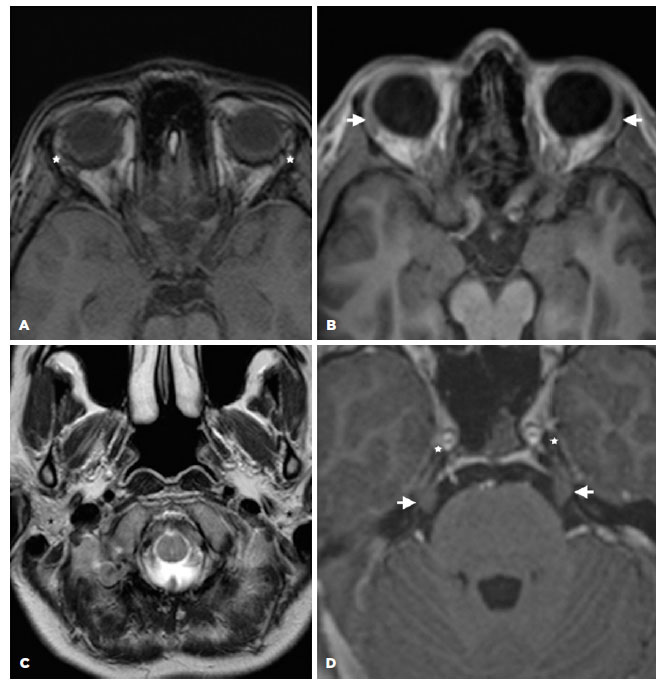

A 77-year-old female presented with DES for five years, which had worsened 12 months before the visit and was attributed to emotional problems. She was using artificial tears and lacrimal punctal plug occlusion. She mentioned a diagnosis of prolactinoma 30 years prior to this visit, which manifested initially with galactorrhea, further confirmed by laboratory and imaging exams. She had been using carbegoline since that diagnosis. Thyroidectomy and systemic arterial hypertension were treated with Puran T4 and hydroclortiazide, respectively. Her physical exam was not remarkable. Her ocular exam was positive for mild bilateral blepharospasm and mild punctate keratitis. The TFBUT was 30 s and the ST was 5 mm OU. Mild MGD with 20% of gland drop out, light expressibility, and cloudy oil secretion were observed. No changes in the eyelid margin, mucocutaneous junction, or gland orifices were observed. The whole salivary flow was 0.02 ml/min. The laboratory exams were normal, including the prolactin and thyroid stimulating hormone (TSH) levels. The anti-Ro/SSA, anti-La/SSB levels were negative. A biopsy of the lip SG revealed moderate acinar atrophy and mild diffuse lymphocytic infiltration, but no focus score. The MRI analysis revea led bilateral atrophy of the LG and the parotid gland (Figure 3). Moreover, a biopsy of the labial SG showed tissue hypotrophy and diffuse lymphocytic infiltration, but not the typical signs of SS, which are foci of lymphocytic infiltration (Figure 3C).

11-fig03tb.jpg)